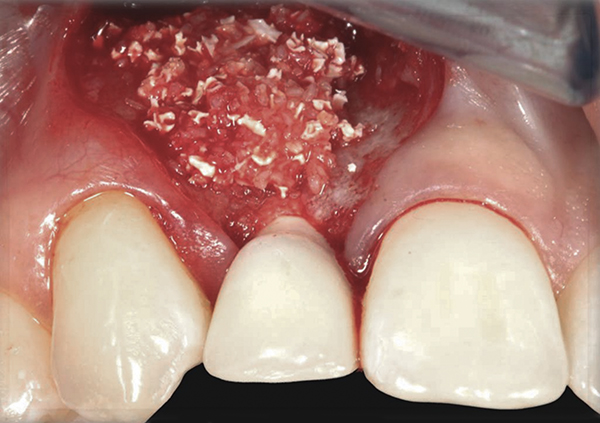

Fig 15. A temporary abutment and crown were inserted. A bone graft was then placed on the buccal aspect to augment the thin buccal bony plate.

Figure 15